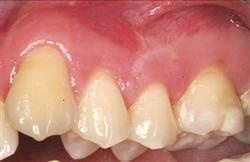

Cosmetic Soft Tissue Grafting

In addition to the functional problems previously mentioned, receding gums can look unsightly.

Longer looking teeth and exposed tooth roots give an "old" appearance to your smile. Some people cover their mouths when they smile for this very reason.